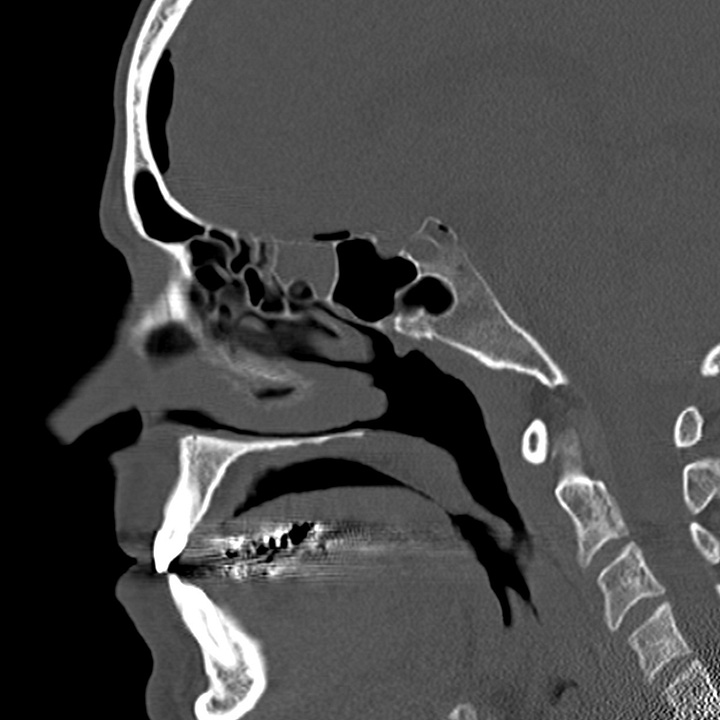

Pneumocephalus following facial trauma with orbital roof and ethmoid fractures. Small amount of air anterior to the right frontal lobe, between the ethmoid bone and the olfactory cortex, and within the right superior orbit. This air is not under tension, but it indicates that the skull base periosteum has been breached and that the subdural space communicates with one of the facial sinuses (in this case the ethmoid air cells). The patient is therefore at increased risk of CSF leak or meningitis.